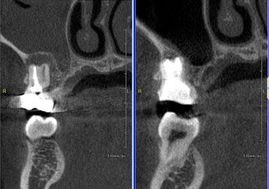

マイクロとCTを使用し根管治療行った症例

CTにてBM2根の存在を確認しマイクロで探索。

骨吸収の改善と根尖病巣からの上顎洞の炎症も改善している。